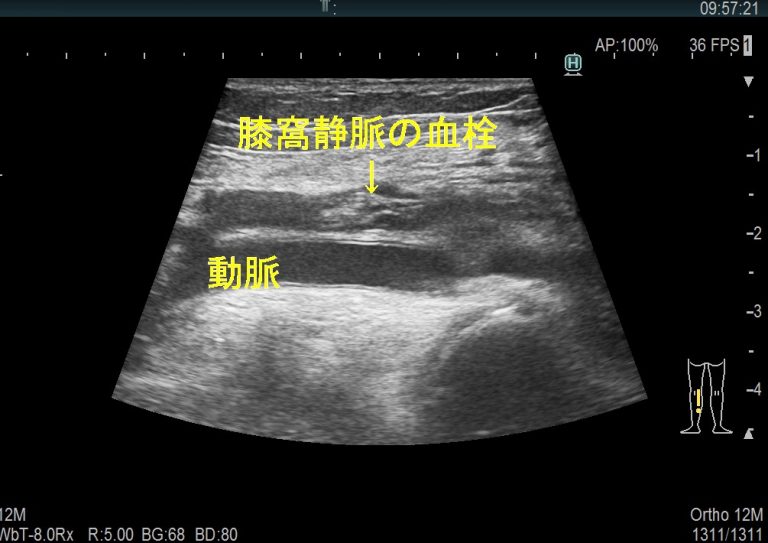

症状の外観や説明だけでは診断を下すのに十分な情報が得られない場合、医師は画像技術を使用して血栓が存在するかどうかを確認することがあります。オプションには、超音波検査、 CT スキャン、および MRI スキャンが含まれます。